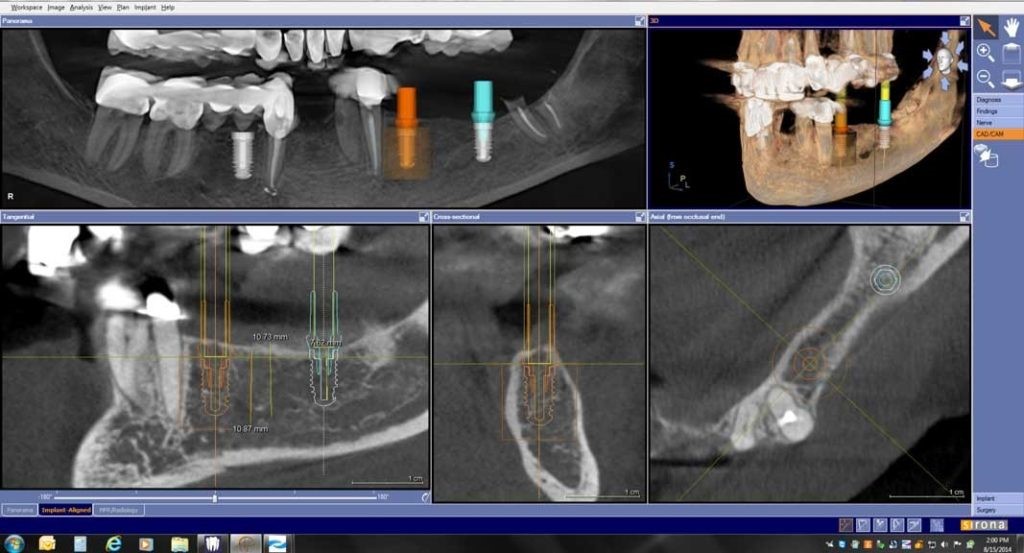

1. Phục vụ cho cấy ghép Implant:

CBCT trong việc lập kế hoạch điều trị Implant sử dụng hình ảnh 3D và đa lớp cắt để xác định chính xác chiều cao, độ rộng và giải phẫu của phần xương hàm và xương ổ răng cũng như mối tương quan vùng mất răng với cấu trúc giải phẫu liền kề như ống thần kinh răng dưới. Đặt Implant với máng hướng dẫn phẫu thuật có thể được thực hiện với các dữ liệu CBCT. Với khả năng 3 chiều của CBCT, các nhà lâm sàng có thể quyết định liệu có cần đến việc ghép xương, nâng xoang trước khi đặt Implant hay không cũng như chọn kích thước implant phù hợp nhất cho từng vùng xương.

Lập kế hoạch đặt implant ảo trên phim CBCT